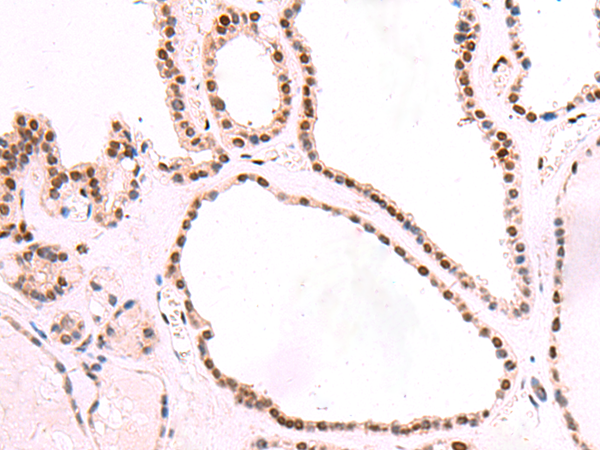

分类: 科研抗体货号: P10144别名: RSE1; SAP130; SF3b130; STAF130应用: IHC反应种属: Human, Mouse